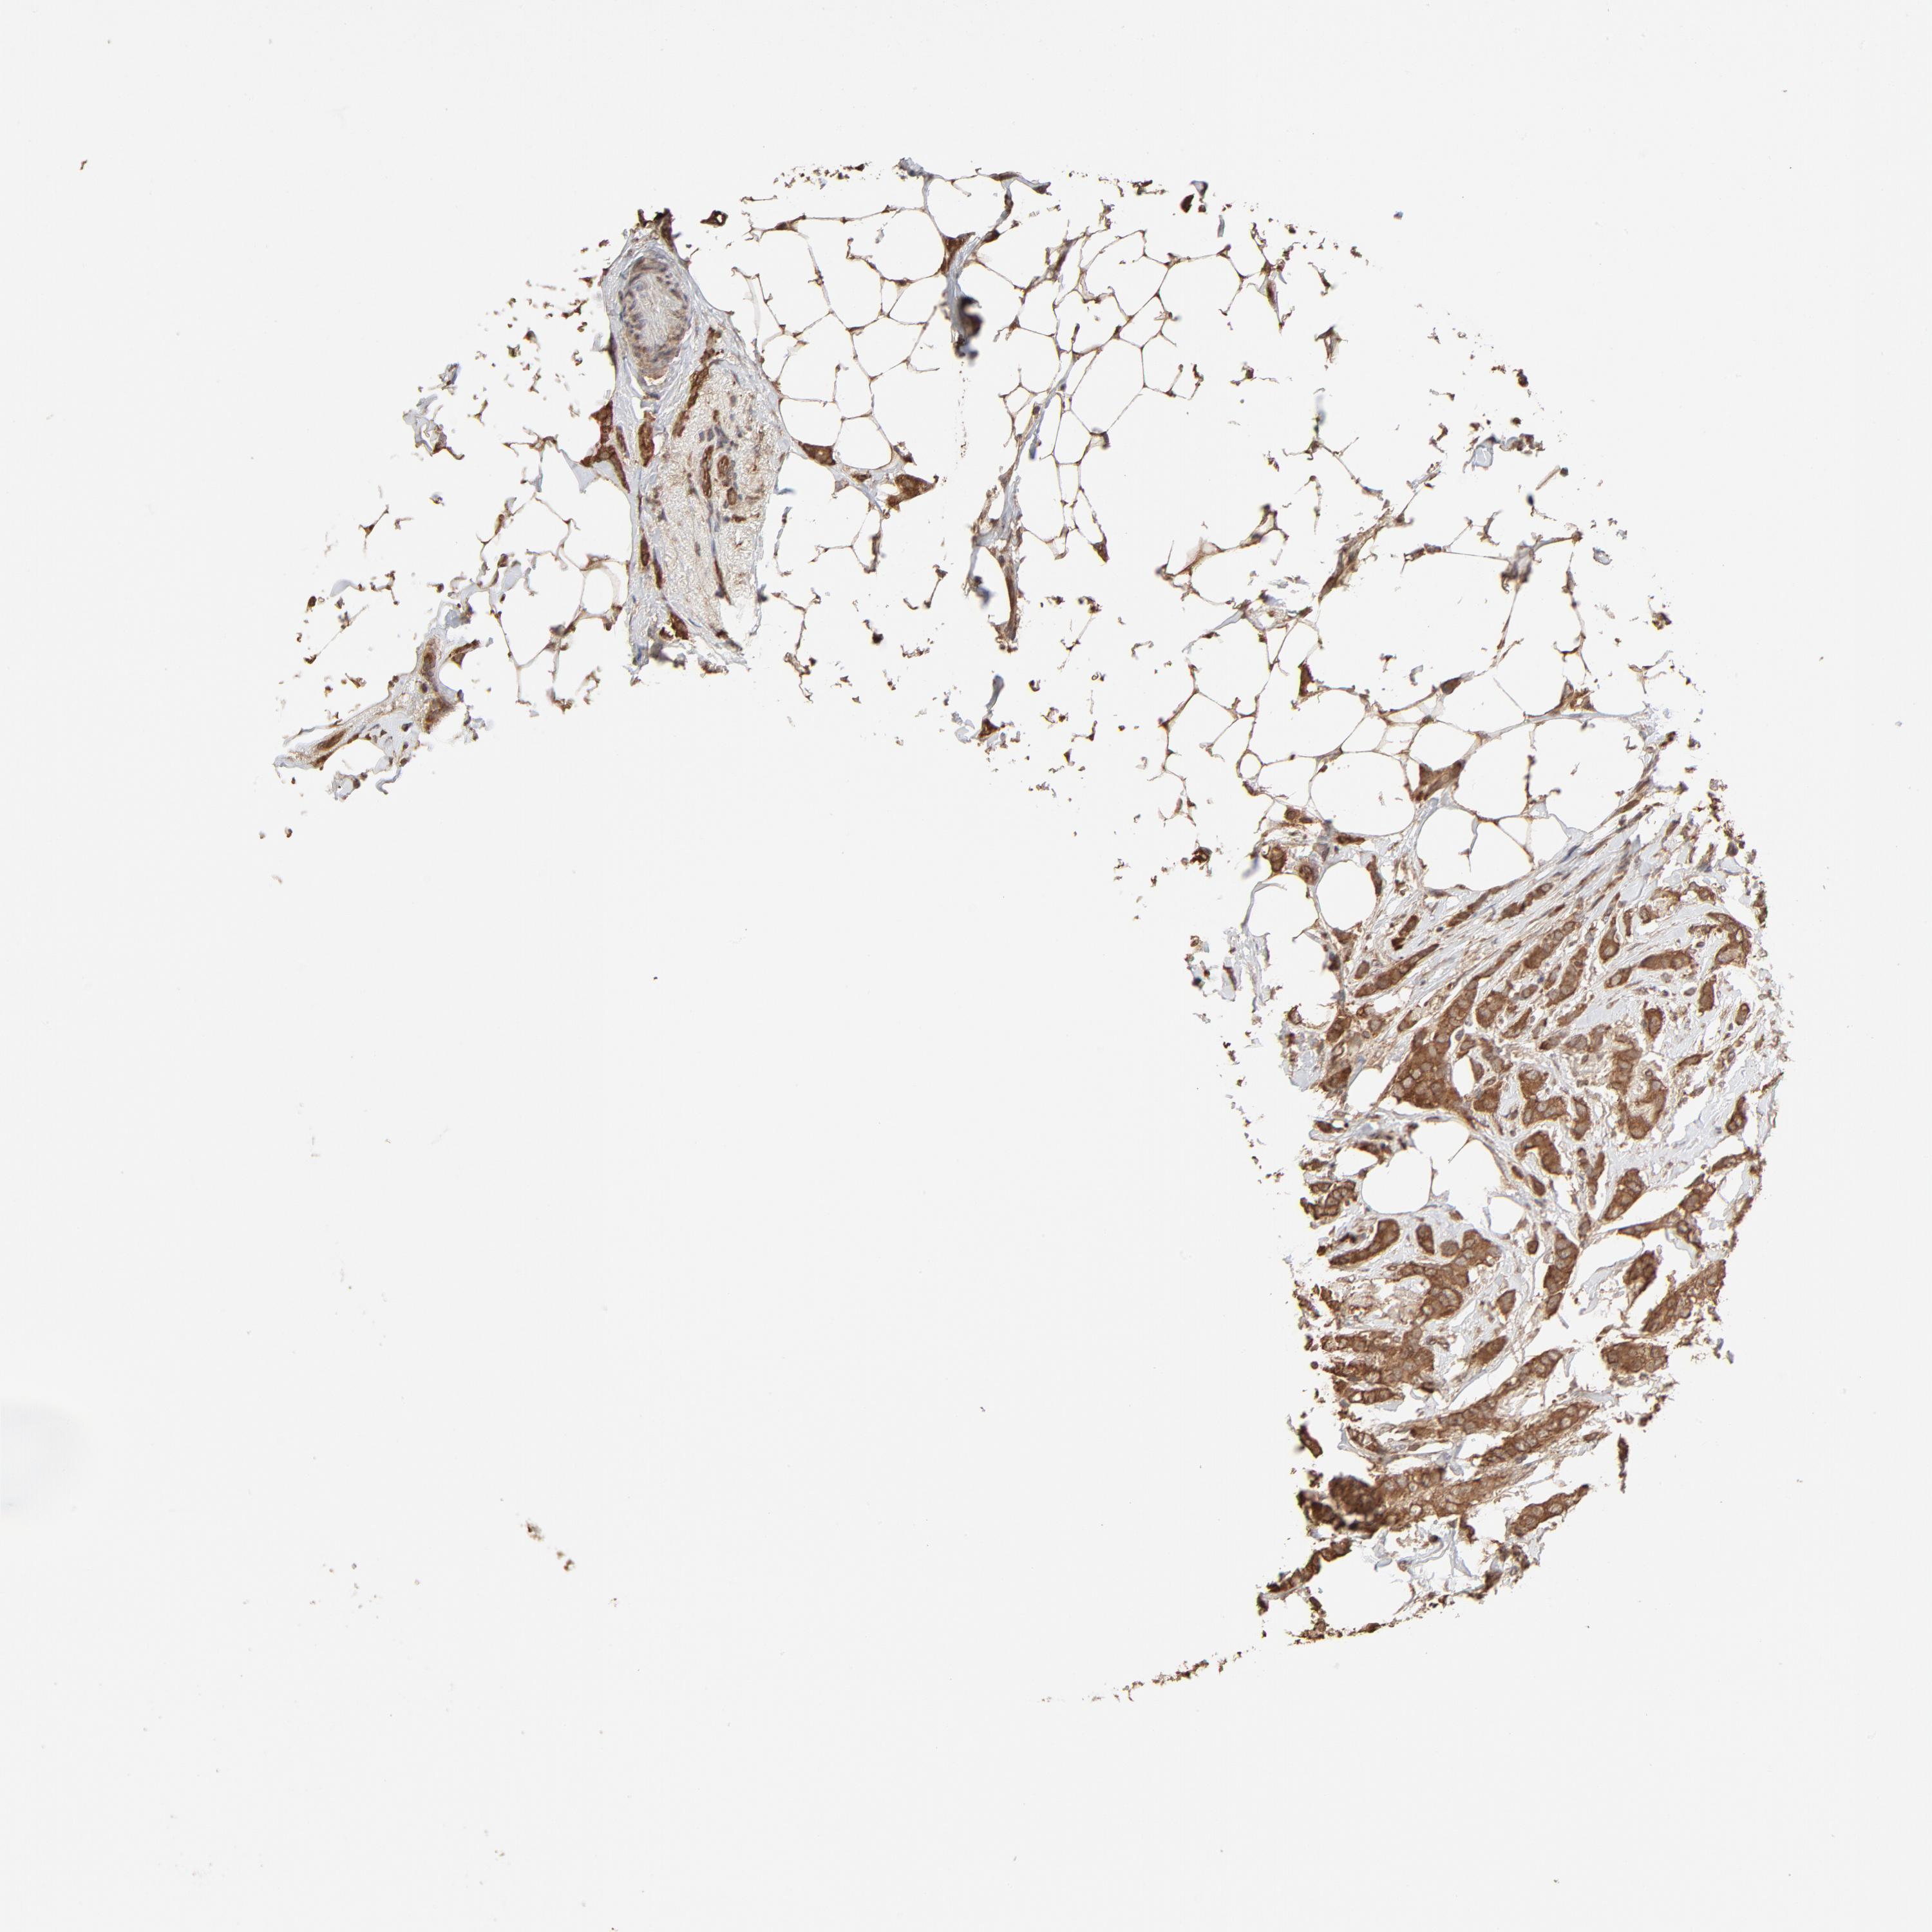

CANCER BREAST CANCER Show tissue menu

BRCA TCGA BRCA VALIDATION PROTEIN EXPRESSION

Breast cancer

Human cancer